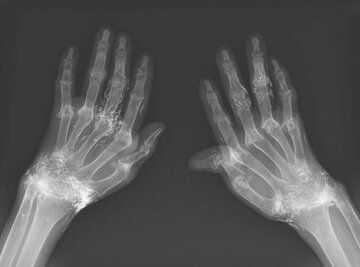

اما این روش هم نهتنها دردی از این زن دوا نکرد، بلکه زانودرد او را هم شدت بخشید. درنهایت او مجبور شد دوباره به بیمارستان مراجعه کند و پزشکان هنگام تصویربرداری از زانوها و دستهای او متوجه صدها رشته ریز و نازک از طلا در بافتهای اطراف زانو و دستهای این زن شدند.

طب سوزنی با رشتههای طلا در برخی از کشورهای آسیایی، بهویژه میان سالمندان، رایج است اما پزشکان هشدار دادند این روش هیچ پشتوانه علمی ندارد و حتی ممکن است موجب عوارض خطرناکی چون ایجاد کیست، جابهجایی نخها در بدن، آسیب به بافتها و حتی اشکال در انجام تصویربرداری MRI شود.